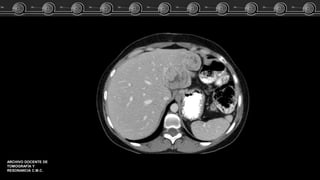

Quistes de desarrollo (simples)

• Son lesiones frecuentes que se encuentran en el 5% al 14% de

la población, > MUJ. Solitarios ó múltiples.

• Masa bien circunscrita, homogénea,

con un VAT próximo al agua, que no

muestra captación al MC.

Quistes de desarrollo(simples) • Son lesiones frecuentes que se encuentran en el 5% al 14% de la población, > MUJ. Solitarios ó múltiples. • Masa bien circunscrita, homogénea, con un VAT próximo al agua, que no muestra captación al MC.